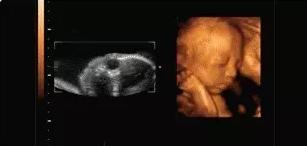

【在妇产科医院,你可以看到这样的胎宝】

本宝宝有些困了——打哈欠